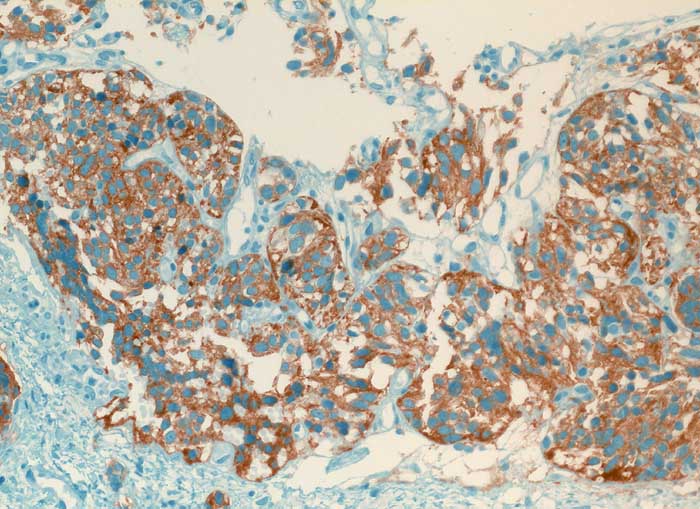

Karzinoid

Lunge

Die spindeligen Tumorzellen exprimieren den endokrinen Marker Synaptophysin.

Histologie

Immunhistochemie

Synaptophysin

200